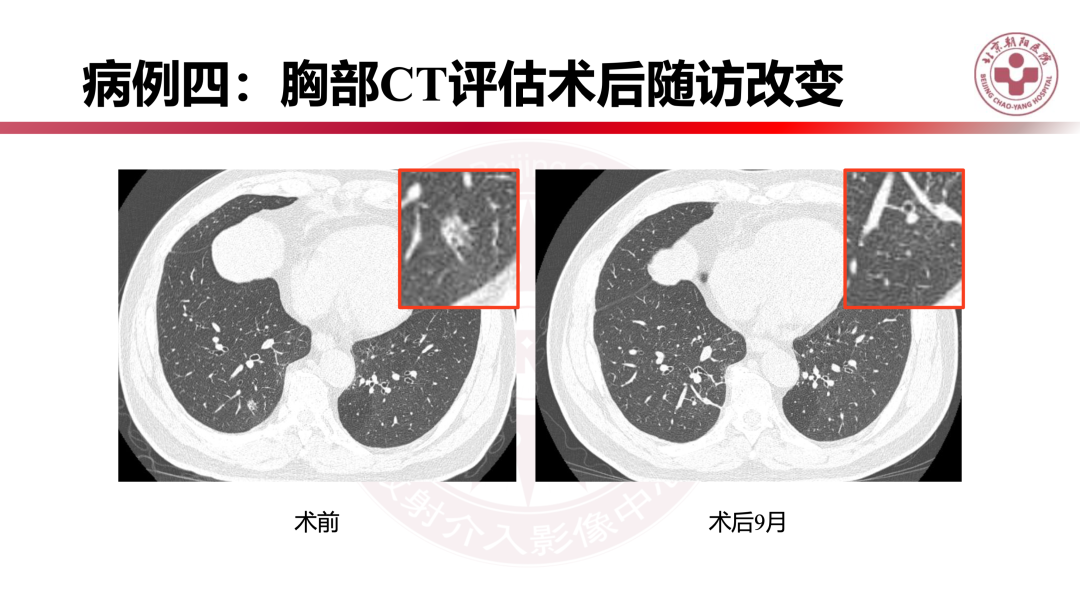

如何诊断早期肺腺癌?|影像读片

来源:北京朝阳医院放射介入影像中心